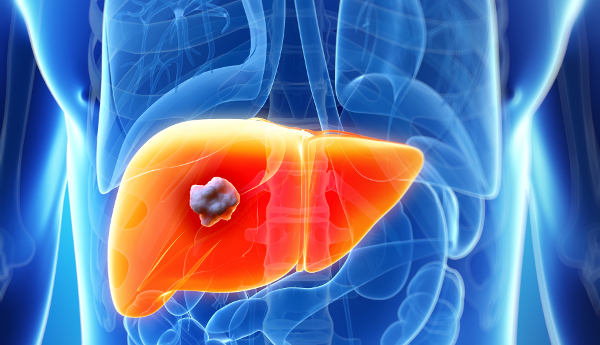

Η θεραπεία ονομάζεται μη αναστρέψιμος ηλεκτρομετασχηματισμός και θεωρείται πολύ καλή για την αντιμετώπιση του καρκίνου στο συκώτι, στο πάγκρεας, στους πνεύμονες κ.α.

Η θεραπεία γίνεται με μια τομή στο μέγεθος της μύτης ενός μολυβιού, από την οποία περνά ένα μικροσκοπικό όργανο που στοχεύει τους όγκους με δυνατά ηλεκτρικά πεδία, τα οποία ανοίγουν μικρές οπές στις μεμβράνες των κυττάρων του καρκίνου. Η θεραπεία αυτή σκοτώνει τους όγκους χωρίς να διαταράσσει την ισορροπία των μορίων που βρίσκονται μέσα και έξω από τα κύτταρα και χωρίς να προκαλεί βλάβες στον υγιή ιστό, επειδή δεν παράγει ούτε κρύο ούτε ζέστη.